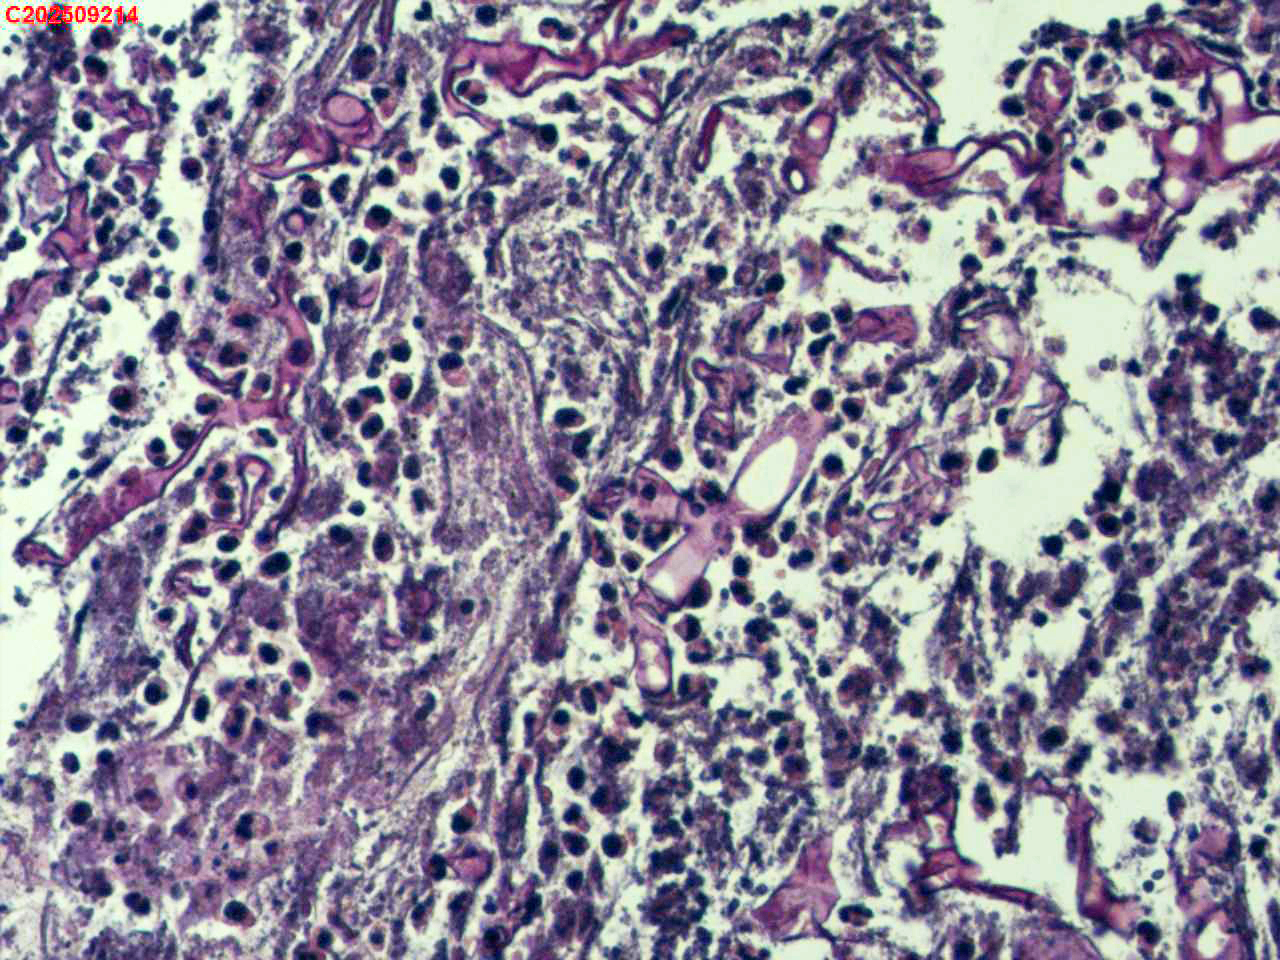

左肺下叶背段咬检组织

性别年龄59岁临床诊断肺结核?肺部感染?

一般病史胸部(平扫):两侧胸廓对称,气管及纵隔居中。双肺纹理增多、紊乱,胸膜下区见多发索条影;双肺见多发大小不等斑片状高密度影,部分呈树芽征样磨玻璃样改变,部分病灶内见支气管含气、少许钙质沉积。气管及大支气管通畅。心脏大小形态可;冠状动脉走行处见多发条形高密度影。双侧胸膜局部肥厚粘连。纵隔内见多发淋巴结影,4L区较大者约10mm* 16mm。

标本名称左肺下叶背段咬检组织

大体所见纤支镜检查:左肺主支气管上叶、下叶及各段级支气管通畅,粘膜无充血,背段外亚段远端可见疑似白色痰栓,灌洗支气管刷检并镜下尝试活检钳清理,发现其质硬考虑为新生物并咬检,该部位深远,且咳嗽及呼吸干扰取材不理想。

毛霉菌病